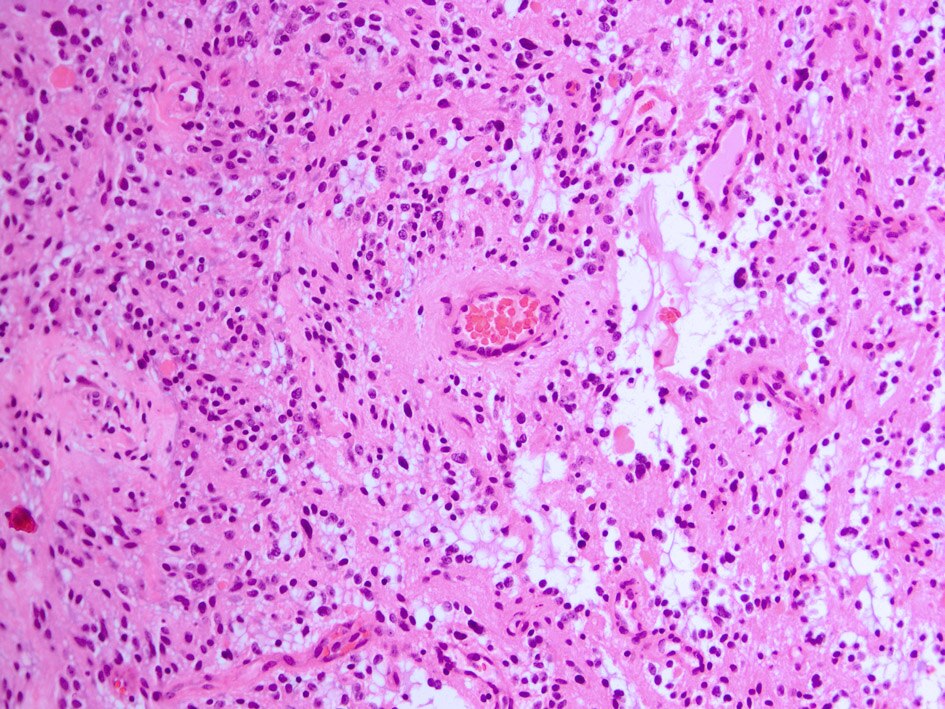

File:Pilomyxoid Astrocytoma HE20x.jpg

| current | 09:22, 9 December 2009 |  | 945 × 709 (372 KB) | Marvin 101 | {{Information |Description={{en|1=Histopathology of pilomyxoid astrocytoma showing astrocytic tumor cells and a myxoid background. Also note angiocentric growthpattern.}} |Source=Own work |Author=Marvin 101 |Date=12-09-2009 |Permission |